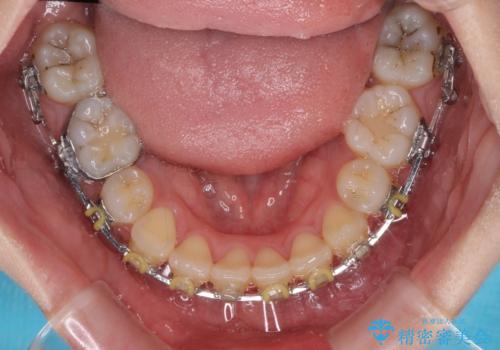

- 地元で抜歯治療を行っている途中、東京へ転職したため治療を継続して欲しいとのことで来院された患者様です。

出っ歯を抜歯矯正にて治療をしていらっしゃいましたが、抜歯スペースが少し残っていたため、閉じて歯列を仕上げていくこととしました。